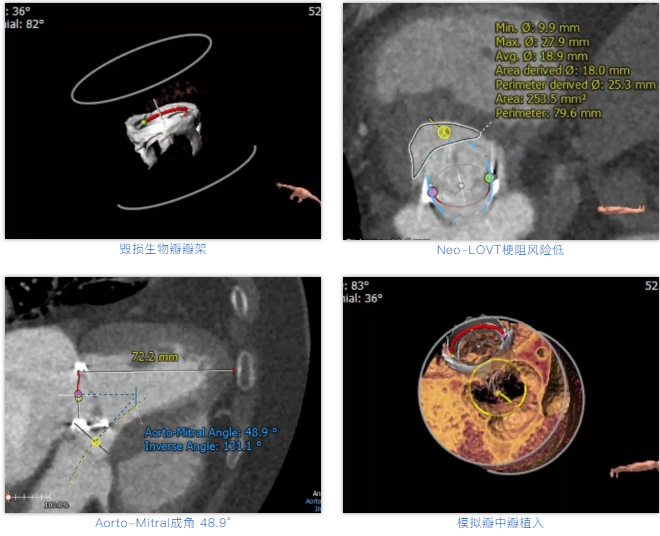

术前经详尽评估患者病情,通过CT重建测量瓣环直径、左室流出道面积。考虑到之前经房间隔入路外科换瓣,房间隔瘢痕严重,最终采用经心尖途径植入25# Renato球扩式瓣中瓣。手术顺利,瓣中瓣植入位置理想,功能表现出色,二尖瓣峰值流速由术前2m/s下降至1.4m/s,平均跨瓣压差由术前10mmHg下降至2mmHg,左室流出道压差正常,经食道超声观察无明显瓣中及瓣周返流。

术前经详尽影像学重建和评估,CT重建测量瓣环直径,评估冠脉梗阻风险及外周血管条件。最终采用经股动脉入路植入21# Renato球扩式瓣中瓣。手术顺利,瓣中瓣植入位置理想,功能表现出色,主动脉瓣峰值流速由术前4m/s下降至2m/s,平均跨瓣压差由术前40mmHg下降至6mmHg。经食道超声观察无瓣周漏及瓣中反流。